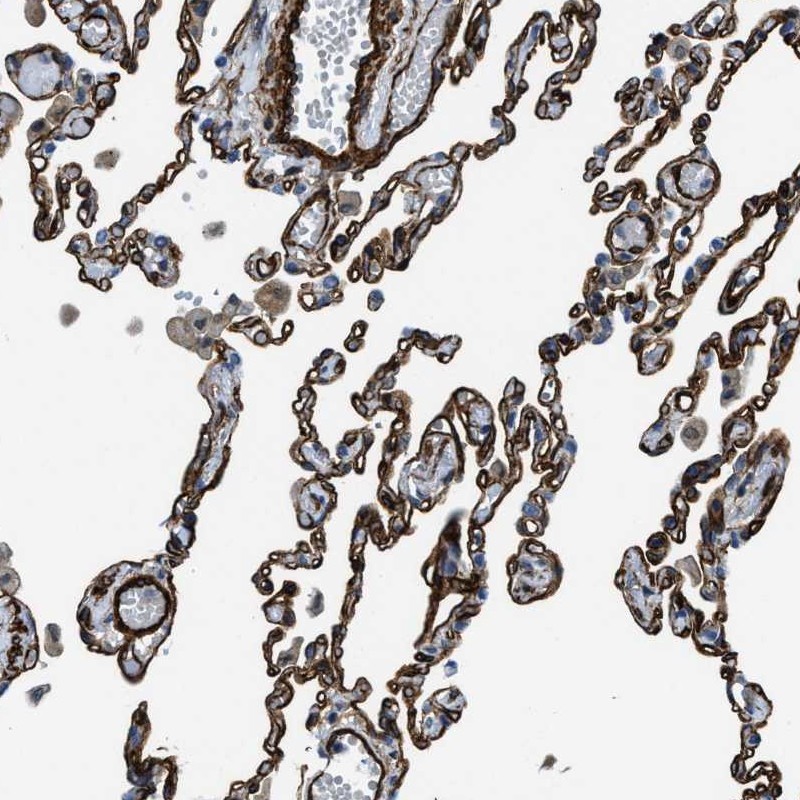

Immunohistochemical staining of human lung shows strong membranous positivity in pneumocytes.